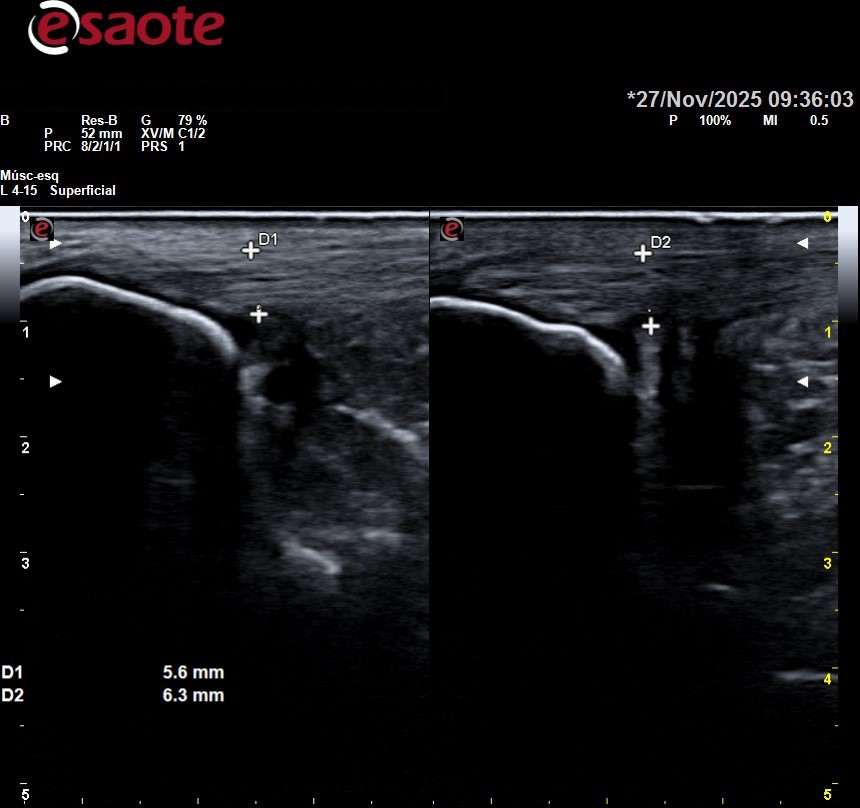

“La ecografía permite estudiar los tejidos por debajo de la piel con precisión milimétrica sin abrirla con el bisturí, valorando si hay lesión en los mismos o no, para centralizar adecuadamente el tratamiento”.

- La ecografía permite visualizar en tiempo real la estructura interna del pie, incluyendo huesos, músculos, ligamentos, tendones y tejidos blandos. Esto facilita la identificación precisa de patologías como fascitis plantar, tendinitis, neuromas, quistes, entre otras.

- La ecografía permite monitorear la evolución de las lesiones y la respuesta al tratamiento de manera no invasiva, lo que ayuda a ajustar el plan terapéutico según sea necesario.